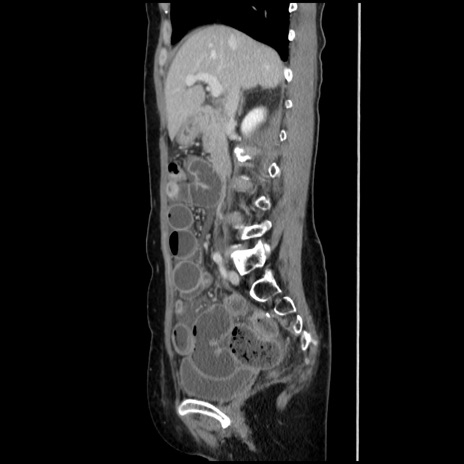

症例32(矢状断像)

【症例】40歳代 女性

【主訴】上腹部痛、嘔気・嘔吐

【現病歴】約9時間前頃から急に上腹部痛、嘔気、嘔吐が出現。改善しないため救急要請。

【既往歴】子宮頚癌(広汎子宮全摘術、放射線療法)、腸閉塞

【身体所見】腹部:平坦、軟、腸雑音亢進、上腹部を中心に腹部全体に圧痛あり。

【データ】WBC 8400、CRP 0.03